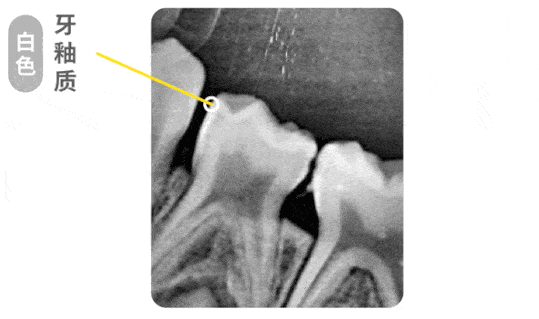

浅龋x线

龋齿分为浅龋→中龋→深龋,然后再发展,就是牙髓炎了.